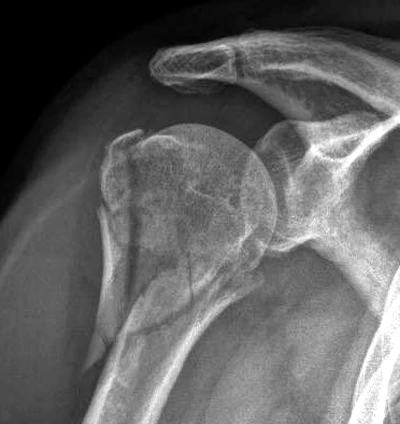

Fractura de Hombro

El hombro está compuesto, entre otras cosas, por tres (3) huesos: el húmero, o hueso del brazo, que va hasta el codo; el omóplato o escápula, que sujeta al hombro y está atrás de las costillas; y la clavícula, que va desde el pecho hasta el hombro.

Una fractura es la rotura parcial o total de cualquiera de los huesos mencionaos. Es decir, que el hueso fracturado está rajado o partido.

Primero se evalúa a la persona y se diagnostica la fractura, generalmente mediante rayos X.